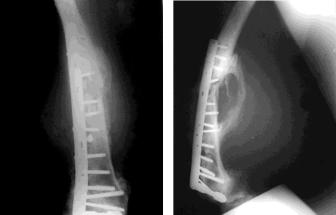

Развитие травматического остеомиелита характеризуется появлением симптомов, свойственных острому остеомиелиту. Основным методом диагностики этой формы остеомиелита является рентгенологический (рис. 59).

Рис. 59. Рентгенограммы при хроническом остеомиелите

бедренной кости после металлоостеосинтеза перелома

Лечение его в острой стадии заболевания мало отличается от лечения, применяемого при остром гематогенном остеомиелите. При длительном течении процесса и переходе его в хроническую стадию с образованием свищей и отхождением секвестров применяют хирургическое лечение, направленное на ликвидацию причины, поддерживающей этот процесс, – удаление костных секвестров, металлоконструкций, а также санацию гнойной полости.